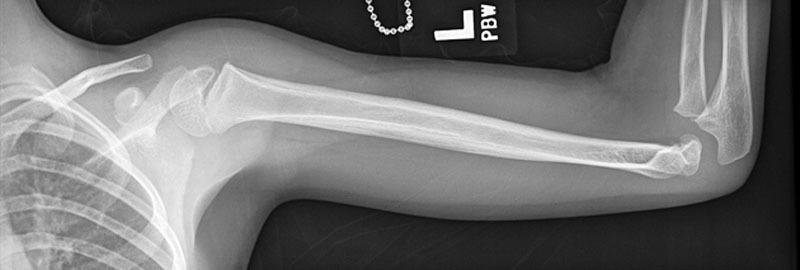

Near-complete Humerus Reconstruction in the Pediatric Patient with Vascularized Free Fibula Transfer.

Vascularized free fibula transfer remains the gold standard for reconstruction of large segmental diaphyseal defects of the upper extremity. In the pediatric patient, before skeletal maturity, free fibula transfer with the fibular head provides an active physis for growth and an articular interface for glenohumeral joint reconstruction. Clinical and cadaveric studies have demonstrated that the vascular supply to the fibular head originates, in most cases, from the anterior tibial system. However, anatomical variation exists, and we report a case in which a vascularized fibula autograft including the physis was transferred on the peroneal artery in a 5-year-old patient with Ewing's sarcoma. At 15-month follow-up, the patient has functional range of motion of the shoulder.